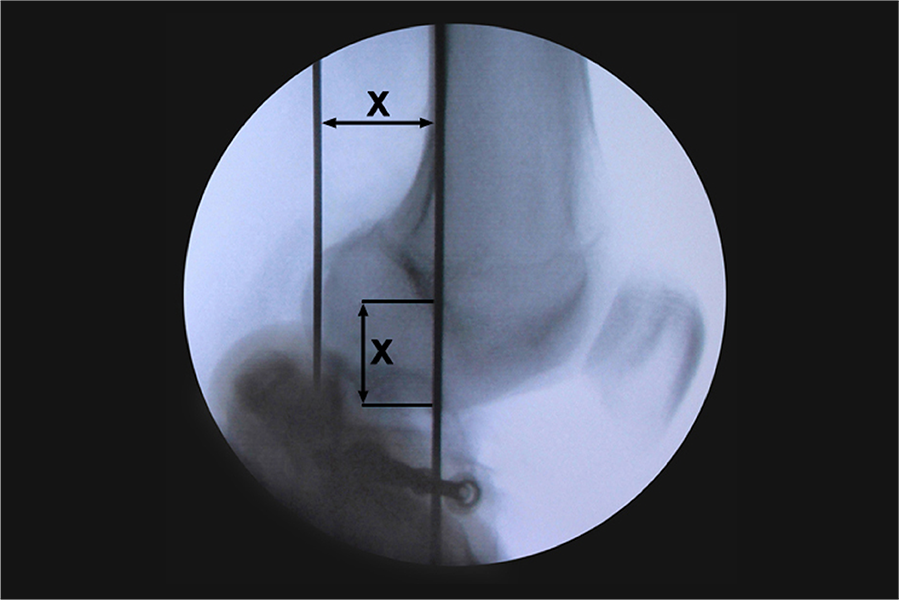

Knee articulated external fixator assemblyKnee rotation center

Componente articular radiotransparente Identificación más sencilla e instantánea del centro de rotación